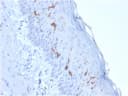

At least five CD1 genes (CD1a, b, c, d, and e) are identified. CD1 proteins have been demonstrated to restrict T cell response to non-peptide lipid and glycolipid antigens and play a role in non-classical antigen presentation. CD1a is a non-polymorphic MHC Class 1 related cell surface glycoprotein, expressed in association with Beta-2 microglobulin. Anti-CD1a labels Langerhans cell histiocytosis (Histiocytosis X), extranodal histiocytic sarcoma, a subset of T-lymphoblastic lymphoma/leukemia, and interdigitating dendritic cell sarcoma of the lymph node. When combined with antibodies against TTF-1 and CD5, anti-CD1a is useful in distinguishing between pulmonary and thymic neoplasms since CD1a is consistently expressed in thymic lymphocytes in both typical and atypical thymomas, but only focally in 1/6 of thymic carcinomas and not in lymphocytes in pulmonary neoplasms. Anti-CD1a is reported to be a new marker for perivascular epithelial cell tumor (PEComa).Primary antibodies are available purified, or with a selection of fluorescent CF® Dyes and other labels. CF® Dyes offer exceptional brightness and photostability. Note: Conjugates of blue fluorescent dyes like CF®405S and CF®405M are not recommended for detecting low abundance targets, because blue dyes have lower fluorescence and can give higher non-specific background than other dye colors.Synonyms:

IHC, FFPE (verified)Validated Applications:

IHC, FFPEField of Research:

CancerPositive Control:

MOLT-4 cells. Paracortex in a tonsil or a reactive lymph node.Concentration: